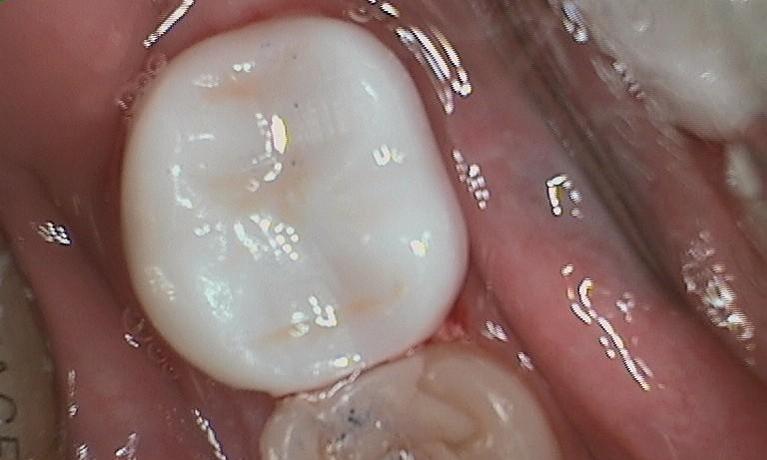

We like to use the white filling material for a few reasons. First we like them because they blend in very nice and look better. Second, we like them because these white fillings act like glue and hold the tooth together. This is known as "bonding." Even if we bond a booth together with a tooth colored filling, overtime this tooth can still breakdown if the filling is large enough. The before photo show a piece of tooth that has broken away from the tooth colored filling. In the same photo, the brown part of the tooth is where ...